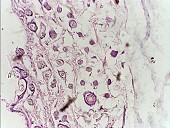

新明穴皮下组织铺片,胆碱酯酶反应,方框内脂肪细胞与细神经紧邻 |